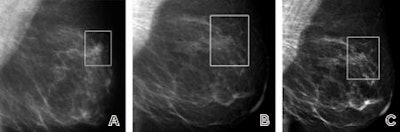

| Fatty breast depicted on (A, D, G) film-screen and (B, C, E, F, H, I) digital left mammograms obtained in 53-year-old woman. Cancerous areas are outlined in rectangles. (A-F) Mediolateral oblique and (G-I) craniocaudal views are shown. The cancer, a mass that proved to be an invasive ductal carcinoma, is much more apparent on the film-screen images than on the digital images, with visibility being greatest on the film-screen mediolateral oblique views. The difference in lesion visibility between the film-screen and digital mammograms is accentuated when the film-screen overview image (A) is compared with the digital overview image obtained by using the default image processing algorithm (B). Close-up views of cancerous areas outlined in A (D) and B (E) are shown. There is a slight improvement in the visibility of the lesion depicted at digital mammography performed by using the Premium View image processing software, as seen on digital mediolateral oblique overview (C), film-screen mediolateral oblique close-up view (D), and digital craniocaudal (I) images. |